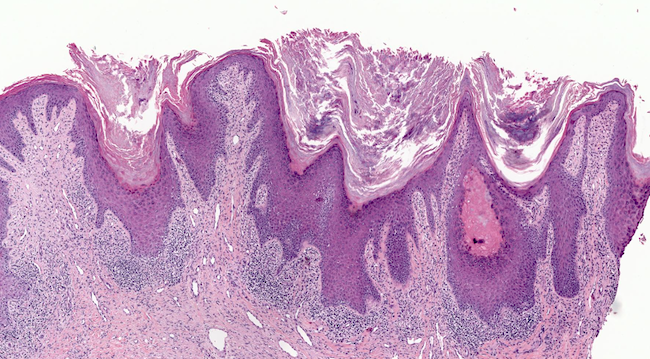

Q

What can be seen in this tissue, and comment on its malignant potential?

A

Severe dysplasia extending from basal third to upper third. Severe Atypia and numerous mitosis.

Severe chance of malignant potential.